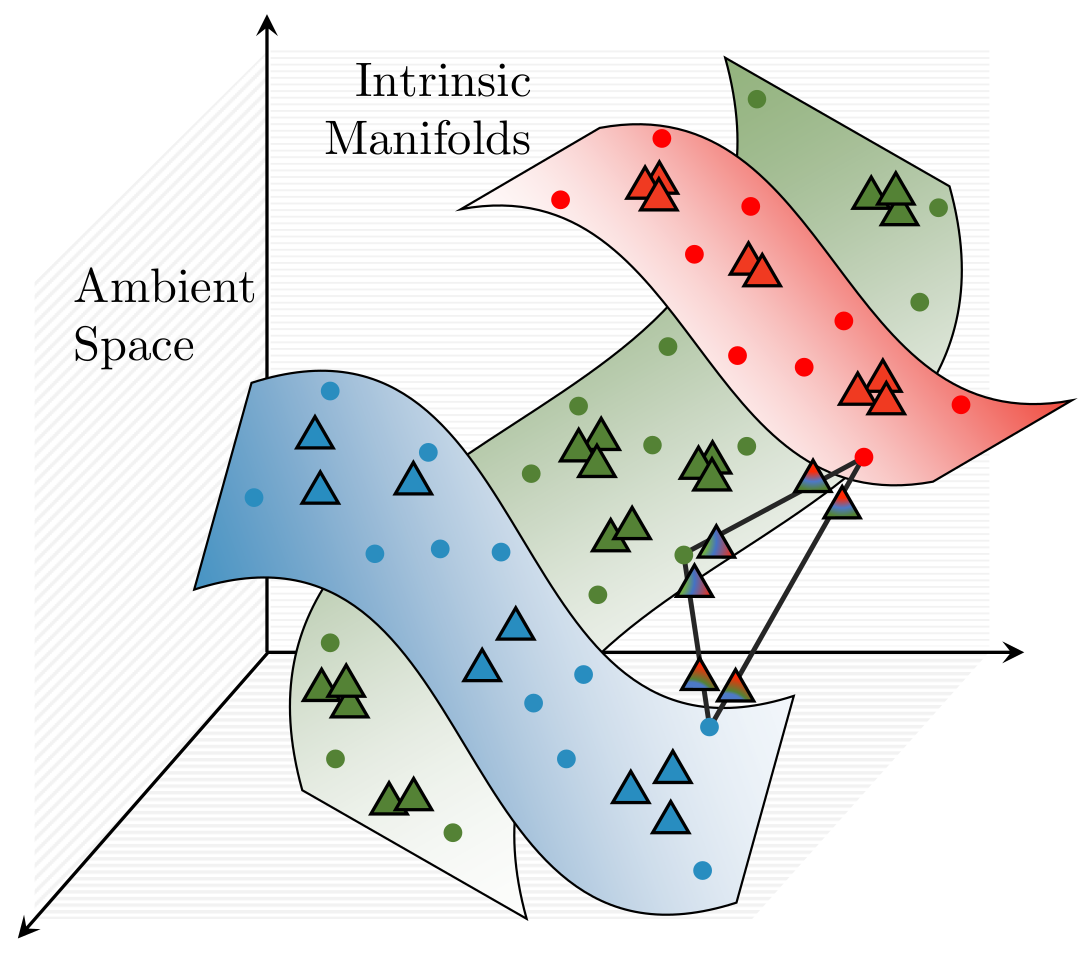

Multi-Sample ζ-mixup: Richer, More Realistic Synthetic Samples from a p-Series Interpolant

Kumar Abhishek, Colin J. Brown, Ghassan Hamarneh

Journal of Big Data, 2024 We propose a generalization of mixup with provably and demonstrably desirable properties that allows convex combinations of more than 2 samples. [Abstract] [BibTeX]

Modern deep learning training procedures rely on model regularization techniques such as data augmentation methods, which generate training samples that increase the diversity of data and richness of label information. A popular recent method, mixup, uses convex combinations of pairs of original samples to generate new samples. However, as we show in our experiments, mixup can produce undesirable synthetic samples, where the data is sampled off the manifold and can contain incorrect labels. We propose ζ-mixup, a generalization of mixup with provably and demonstrably desirable properties that allows convex combinationsof T ≥ 2 samples, leading to more realistic and diverse outputs that incorporate information from T original samples by using a p-series interpolant. We show that, compared to mixup, ζ-mixup better preserves the intrinsic dimensionality of the original datasets, which is a desirable property for training generalizable models. Furthermore, we show that our implementation of ζ-mixup is faster than mixup, and extensive evaluation on controlled synthetic and 26 diverse real-world natural and medical image classification datasets shows that ζ-mixup outperforms mixup, CutMix, and traditional data augmentation techniques.

ζ-mixup: Richer, More Realistic Mixing of Multiple Images

Kumar Abhishek, Colin J. Brown, Ghassan Hamarneh

Medical Imaging with Deep Learning (MIDL) Short Paper, 2023 We present a multi-sample Riemann zeta-weighted mixing-based image augmentation to generate richer and more realistic outputs. [Abstract] [BibTeX] [Presentation Slides] [Poster]

Data augmentation (DA), an effective regularization technique, generates training samples to enhance the diversity of data and the richness of label information for training modern deep learning models. mixup, a popular recent DA method, augments training datasets with convex combinations of original samples pairs, but can generate undesirable samples, with data being sampled off the manifold and with incorrect labels. In this work, we propose ζ-mixup, a generalization of mixup with provably and demonstrably desirable properties that allows for convex combinations of N ≥ 2 samples, thus leading to more realistic and diverse outputs that incorporate information from N original samples using a p-series interpolant. We show that, compared to mixup, ζ-mixup better preserves the intrinsic dimensionality of the original datasets, a desirable property for training generalizable models, and is at least as fast as mixup. Evaluation on several natural and medical image datasets shows that ζ-mixup outperforms mixup, CutMix, and traditional DA methods.